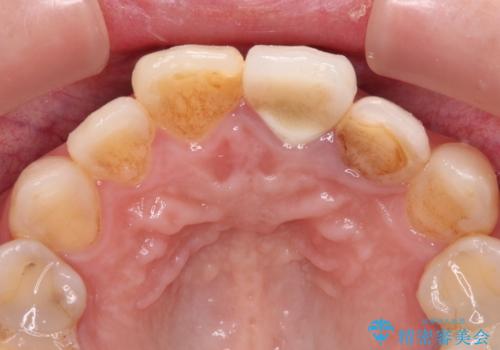

- 以前に他院で装着した前歯のオールセラミッククラウンが気になるとのことで来院された患者様です。

真ん中のオールセラミッククラウンを正面から見ると大変自然に仕上がっているのですが、側方から見ると白色が強く、さらには隣の歯は神経が除去されて変色していたため、コントラストでより色の違いが際立っていました。

前歯2本をオールセラミッククラウンにて補綴治療することとしました。